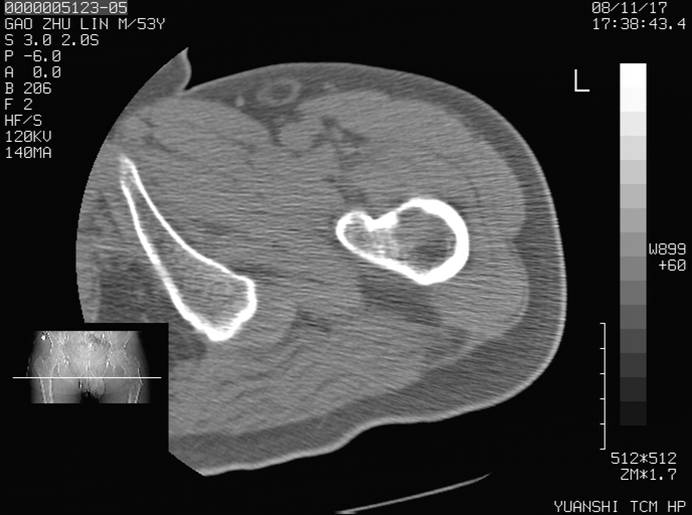

标题: CT16696:M53Y,左股骨上段骨折。 [打印本页]

标题: CT16696:M53Y,左股骨上段骨折。

左股骨上段外伤1个小时,左股骨上段疼痛。村医以腰椎间盘病变给以按摩及理疗数天。

图像不太清楚,左股骨上段外伤性骨折?病理性骨折?

左股骨上段粉碎性骨折

左股骨上段粉碎性骨折;建议上传骨窗看看是不是病理性的啊!

左股骨上段粉碎性骨折,不排除病理性骨折可能。

考虑骨肉瘤伴病理骨折

考虑:骨肉瘤伴病理骨折.

病理性骨折,考虑转移所致.

左股骨上段粉碎性骨折,不排除病理性骨折可能